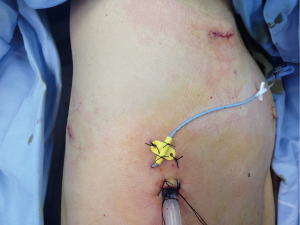

We apply general anesthesia and double-lumen trachea cannula routinely. In order to achieve a better analgesic Port placement effect for facilitating cough and expectoration during the perioperative period and to leave an observation hole after the surgery (leaving a postoperative drainage tube) and continuous intercostal nerve block (Figure 3).

We apply a 3-hole operation: the observation hole of thoracoscope is chosen to be located between the midaxillary line and the posterior axillary line of the 8th intercostal space with a length about 1.5 cm; the main operation incision is located between the anterior axillary line and the posterior axillary line of the 3rd intercostal space (limited to excision of the upper right pulmonary lobe) with a length about 3 cm. Apply protective cover of incision to protect the main operation incision during the surgery to be convenient for in-and-out of instrument and preventing tumor deposit; the auxiliary operation hole is chosen to be in the the 9th intercostal space of the scapular line with a length about 1.5 cm. After finish making incisions, first explore the chest roundly, separate the adhesion and after excluding special conditions such as metastasis in the chest, start the surgery. Decide whether to carry out pulmonary lobectomy according to results of frozen sections.